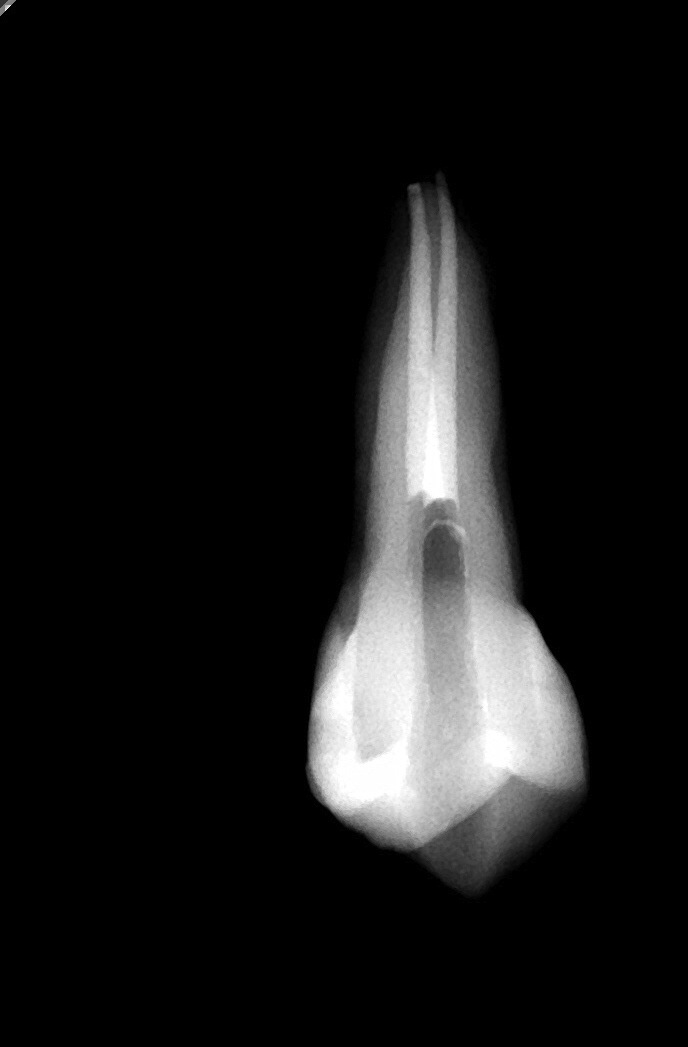

昨日、今日とめがねザル東京のお茶の水にいました。なぜなら、歯の根っこの病気を治す勉強会に参加するためです。

6月にもペン大の理論を学びに、石井歯内療法研究会の講義を2日間受けたのですが、今回はその実践なのです。

しかし、根管治療は根がまっすぐなめがねザルには地道にできて、しかも細かくきちんとできているか問われるので、とても好きな治療なのです。これでもかとしても、まだまだ奥が深いのが根管治療。